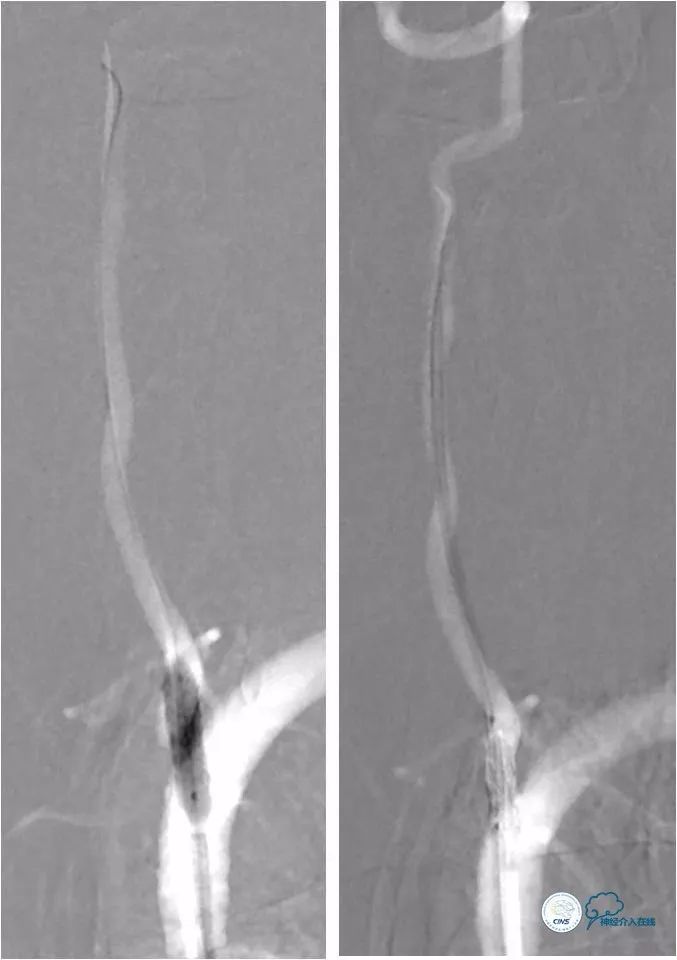

将Transend微导丝(0.014″,300cm)在Echelon-10微导管帮助下放置于左大脑后动脉P2段,予以Gateway球囊(2×9mm)预扩张病变(图13)。

图13

后置入Wingspan自膨式支架(3.5×15mm),造影提示支架释放后支架贴壁良好,前向血流TICI 3级(图14)。

图14